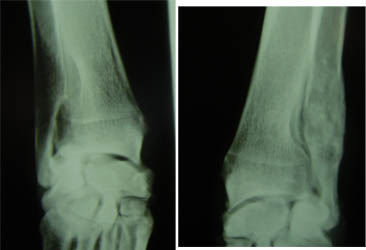

Röntgenbild des medialen Gleichbeins bei einem 2-jährigen Maultier. Man sieht eine feine Linie zwischen den beiden Pfeilen. Klinisch sieht man eine leichte Lahmheit. Der Besitzer informiert uns zusätzlich, dass das Tier auch Hahnenfuss gefressen habe... eine schulmedizinische wie homöopathische Knacknuss! Doch eine Gleichbeinlahmheit, die Gleichbeine sind ja auch ein Teil des Fesselträgers...? Im Röntgenbild sieht man sonst keine Veränderungen. Ist das Ganze ein so genanntes Artefakt?? Ich kenne diese Fragestellung aus meiner chirurgischen Tätigkeit beim Menschen. Wir behandeln homöopathisch, zuerst gegen eine mögliche leichte Vergiftung, dann gegen den eigentlichen Befund ausgehend von einer krankhaften Veränderung im Sehnen-/ Bänderbereich.